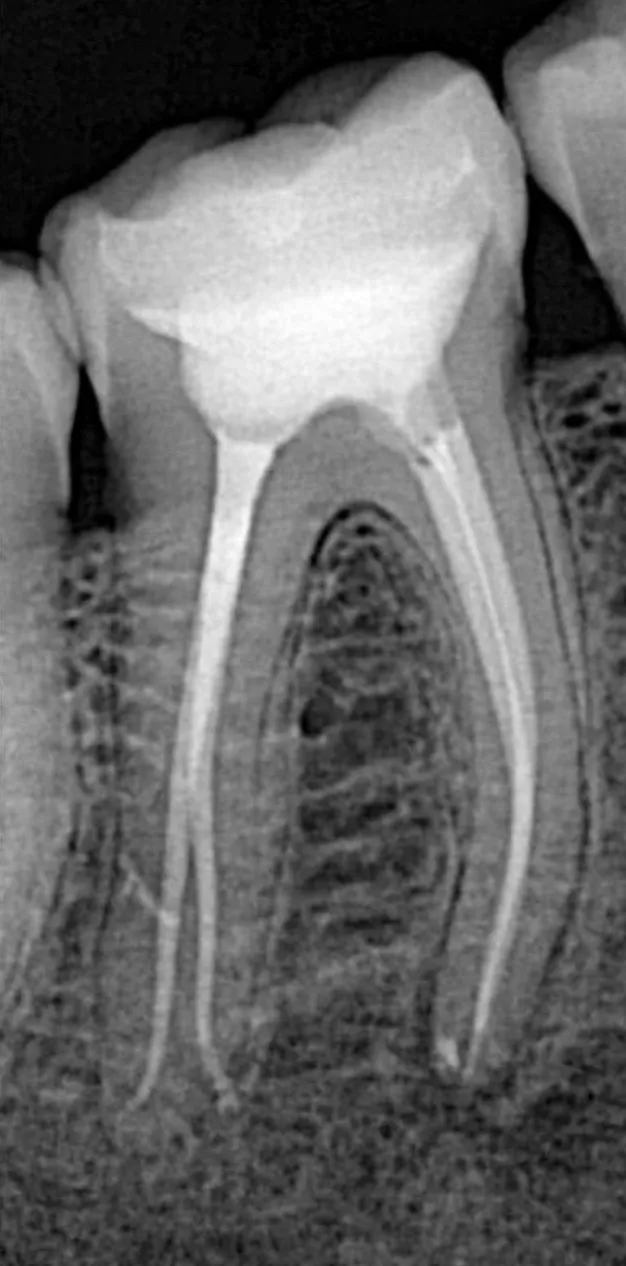

قبل

بعد